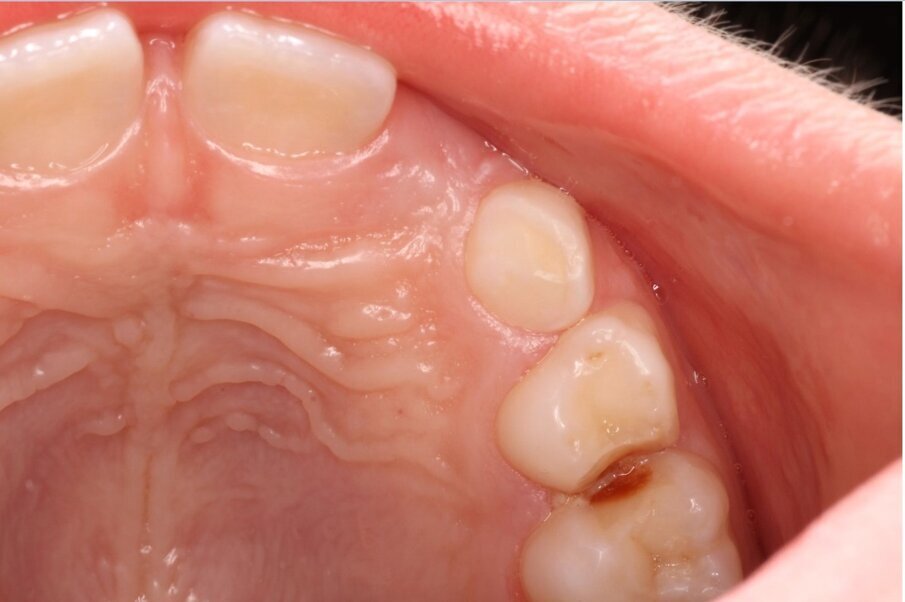

Het eerste kind waarbij wij NRC toepasten was 6 jaar. Op de bitewings werden cariëslaesies bij alle vlakken van de aangrenzende melkmolaren gediagnosticeerd. Met de ouders werd besproken wat onze plannen waren. Zij gingen hiermee akkoord. In de volgende zitting werden de 8 vlakken beslepen (afbeelding 1a-b). De behandeling verliep probleemloos en werd goed geaccepteerd. Maar in het vervolgtraject hebben we steken laten vallen. De voorlichtende communicatie gebeurde hoofdzakelijk traditioneel. De terugkomtermijn besloeg een paar keer achter elkaar een interval van bijna een jaar. Daar verander je geen gedrag mee. De verslaggeving ontbrak een aantal keren. Bijna 6 jaar later werd geconstateerd dat er veel plaque aanwezig was. De wisseling had inmiddels plaatsgevonden. Restauratief of chirurgisch ingrijpen is sinds NRC werd toegepast niet nodig geweest en de bitewings vertonen geen cariësactiviteit (afbeelding 2a-b). Ook waren geen sealants noodzakelijk geweest.

Afbeelding 1a. Beslepen melkmolaren in de bovenkaak (NB het verdient aanbeveling de distale vlakken schuiner te beslijpen dan de mesiale vlakken in verband met de toegankelijkheid voor de tandenborstel).

Afbeelding 1b. Beslepen melkmolaren in de bovenkaak (NB het verdient aanbeveling de distale vlakken schuiner te beslijpen dan de mesiale vlakken in verband met de toegankelijkheid voor de tandenborstel).